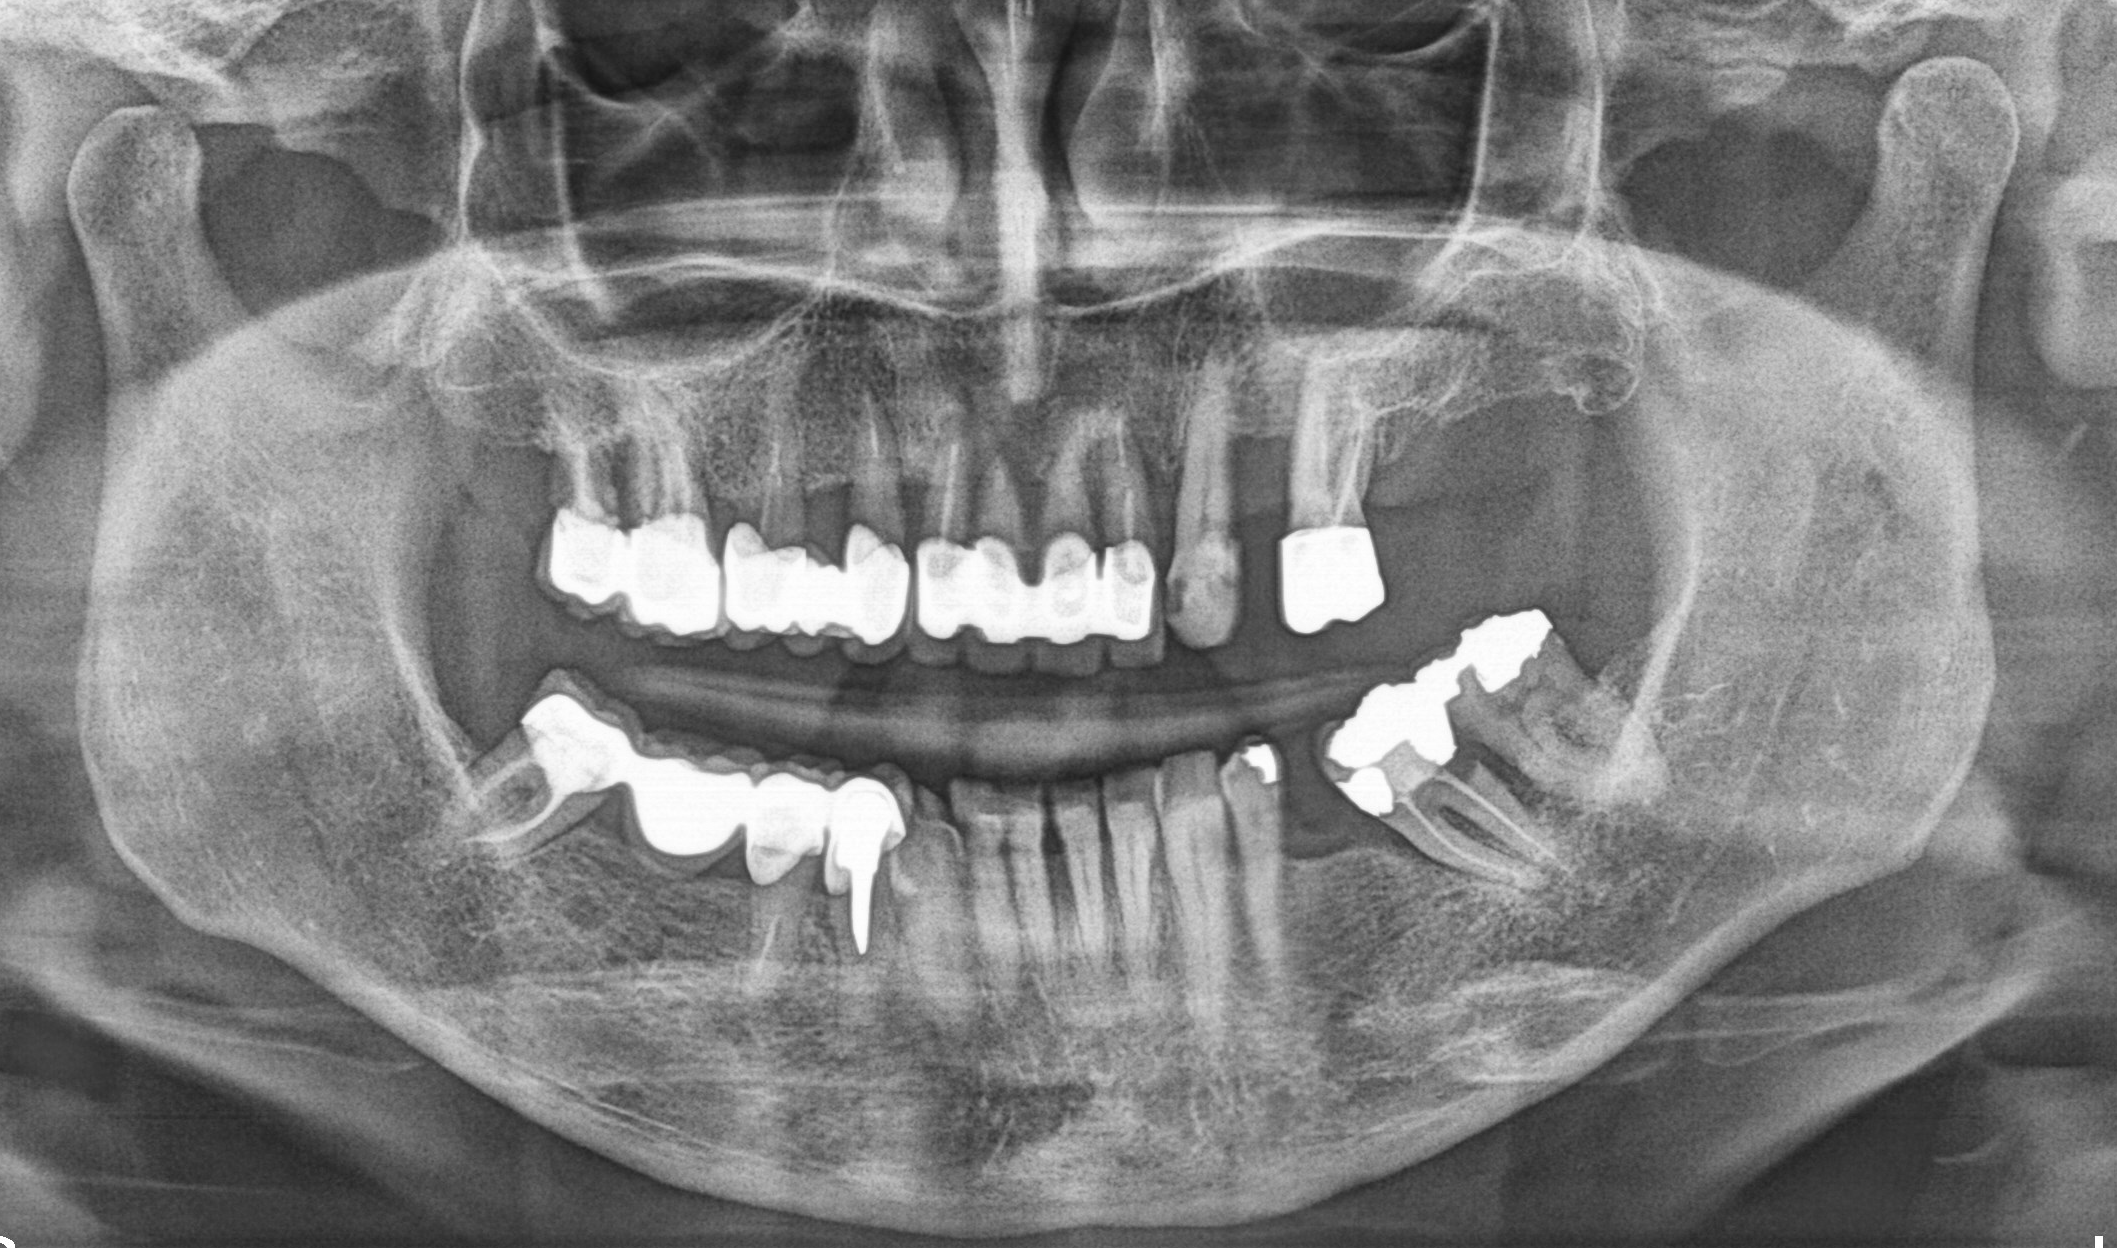

Nei casi più complessi, come quando mancano molti denti, gli elementi presenti non sono recuperabili o è necessario intervenire anche su quantità ridotte di osso, adottiamo tecniche avanzate per ripristinare estetica e funzione. Di seguito presentiamo due tipologie di riabilitazioni complesse che eseguiamo nel nostro studio.

Riabilitazioni complesse con mantenimento

dei denti naturali

In alcune situazioni, anche quando è necessario inserire più impianti, è possibile preservare i denti naturali presenti e valorizzarli con altri trattamenti come ortodonzia, faccette, corone o innesti gengivali. Questo approccio permette di combinare diverse tecniche per ottenere un risultato finale armonioso, funzionale e naturale, rispettando al massimo la struttura dentaria residua.

Caso 3 - Caso 4

PRIMA